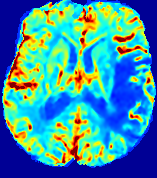

LesionRefer to captionRefer to captionRefer to captionRefer to captionRefer to captionRefer to caption𝐕rgbsubscript𝐕𝑟𝑔𝑏{\bf{V}}_{rgb}Refer to captionRefer to captionRefer to captionRefer to captionRefer to captionRefer to caption𝐕2subscriptnorm𝐕2{\|\bf{V}}\|_{2}Refer to captionRefer to captionRefer to captionRefer to captionRefer to captionRefer to captionRefer to caption3.53.53.52.82.82.82.12.12.11.41.41.40.70.70.70.00.00.0(mm/s)𝑚𝑚𝑠(mm/s)D𝐷DRefer to captionRefer to captionRefer to captionRefer to captionRefer to captionRefer to captionRefer to caption0.0200.0200.0200.0160.0160.0160.0120.0120.0120.0080.0080.0080.0040.0040.0040.0000.0000.000(mm2/s)𝑚superscript𝑚2𝑠(mm^{2}/s)Slice #1Slice #2Slice #3Slice #4Slice #5Slice #6

Figure 4: PIANO feature maps for another patient in the ISLES 2017 training set, where the lesion is located in the right hemisphere. Top row: segmented stroke lesion region (white) on different slices. The corresponding slices for the PIANO feature maps are shown in the following rows.

For a better insight into an estimated velocity field 𝐕𝐕{\bf{V}} and diffusion field 𝐃𝐃{\bf{D}}, we compute the following maps: (1) 𝐕rgbsubscript𝐕𝑟𝑔𝑏{\bf{V}}_{rgb}: Color-coded orientation map of 𝐕=(Vx,Vy,Vz)T𝐕superscriptsuperscript𝑉𝑥superscript𝑉𝑦superscript𝑉𝑧𝑇{\bf{V}}=(V^{x},V^{y},V^{z})^{T}, obtained by normalizing 𝐕𝐕{\bf{V}} to unit length and mapping its 3 components to red, green, blue respectively; (2) 𝐕2subscriptnorm𝐕2\|{\bf{V}}\|_{2}: 222 norm of 𝐕𝐕{\bf{V}}; (3) D𝐷D: scalar field in Eq. 5.

Fig. 3 and Fig. 4 show the PIANO feature maps estimated from two ISLES 2017 patients: all are highly consistent with the lesion in both cases. Details of the blood flow trajectories are revealed in 𝐕rgbsubscript𝐕𝑟𝑔𝑏{\bf{V}}_{rgb} by the ridged patterns and the sharp changes of colors in the unaffected (right) hemisphere, while the flat patterns appearing within the lesion provide little directional information about the velocity and indicate low velocity magnitudes. Velocity magnitudes are more directly visualized via 𝐕2subscriptnorm𝐕2\|{\bf{V}}\|_{2}, from which one can easily locate the lesion where 𝐕2subscriptnorm𝐕2\|{\bf{V}}\|_{2} is low. D𝐷D also indicates lower diffusion values in the lesion, though with less contrast potentially due to the fact that it captures the accumulated effect of CA diffusion at the voxel-level.